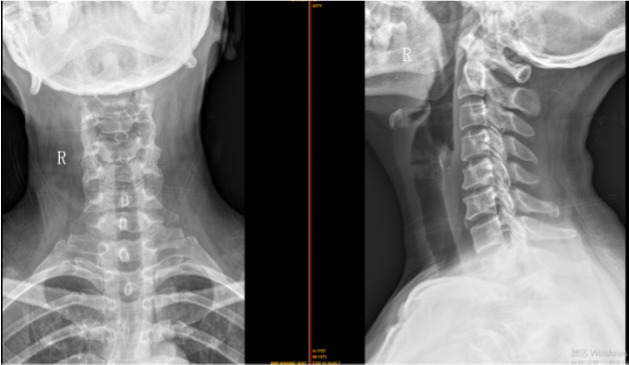

【影像】颈椎X线片报颈椎退行性变,C5椎稍后移位。齿状突与寰椎侧块关节间隙失对称。阅片见颈椎向右侧弯,颈椎平直,C5-6失稳,寰齿侧间隙左侧窄,左侧寰枢外侧关节对合不全,枢椎棘突偏左。

【讨论】患者大椎上方疼痛,查体项僵、肤冷、双侧后斜角肌紧张&压痛(+),X线片颈椎退行性变、向右侧弯、颈椎平直、C5-6失稳,诊断为“颈椎病”。 寰椎左侧横突压痛(+)、右侧头后大直肌紧张&压痛(+),X线片见寰齿侧间隙左侧窄、左侧寰枢外侧关节对合不全、枢椎棘突偏左,诊断为“寰枢关节半脱位”。

患者突然出现头晕、血压升高,无高血压病史,且与颈痛同时出现,考虑“颈源性高血压”。来诊时头晕不重,查体旋颈试验(-),诊断颈源性高血压证据不足。寰枢关节半脱位与颈椎病诊断明确,前者寰椎旋转移位后两侧横突孔分别向前后挤压-牵张椎动脉、C5椎体后移则双侧横突孔向后挤压-牵张椎动脉致椎基底供血不足,引起血压反射性升高。椎基底动脉供血不足则丘脑缺血,影响睡眠-觉醒中枢而睡眠障碍。